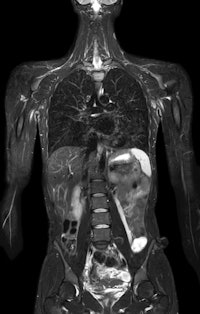

![]() |

| Philips is highlighting its work-in-progress PET/MRI scanner. |

PET/MRI is one of the hottest areas in molecular imaging, and Philips discussed its work in this area at the European Congress of Radiology (ECR) in March. This week at RSNA, the company is showing an actual system gantry and is discussing its plans for commercialization of the technology.

Rather than insert a PET detector array inside a 3-tesla MRI gantry, the Philips approach uses separate MRI and PET gantries with a shared turntable-style patient table in between. The patient is shuttled between the scanners and images are fused during reconstruction. Philips believes this approach minimizes image artifacts that can develop with the PET insert approach.

Philips believes that PET/MRI will demonstrate its value in a number of clinical applications, including areas such as the prostate and breast, which have been more difficult to image with PET/CT. PET/MRI scans are performed with the company's time-of-flight protocols, and MR images are used for attenuation correction as well.

Philips is demonstrating on the RSNA show floor the model it has installed at three beta sites (only a panel display of the scanner was used at the ECR meeting). A 510(k) application is pending for the system, which can also operate as a standard 3-tesla MRI scanner. This latter point is key, as PET/MRI is currently not reimbursable in the U.S., so users can continue to use the hybrid system for separate MRI and PET studies.